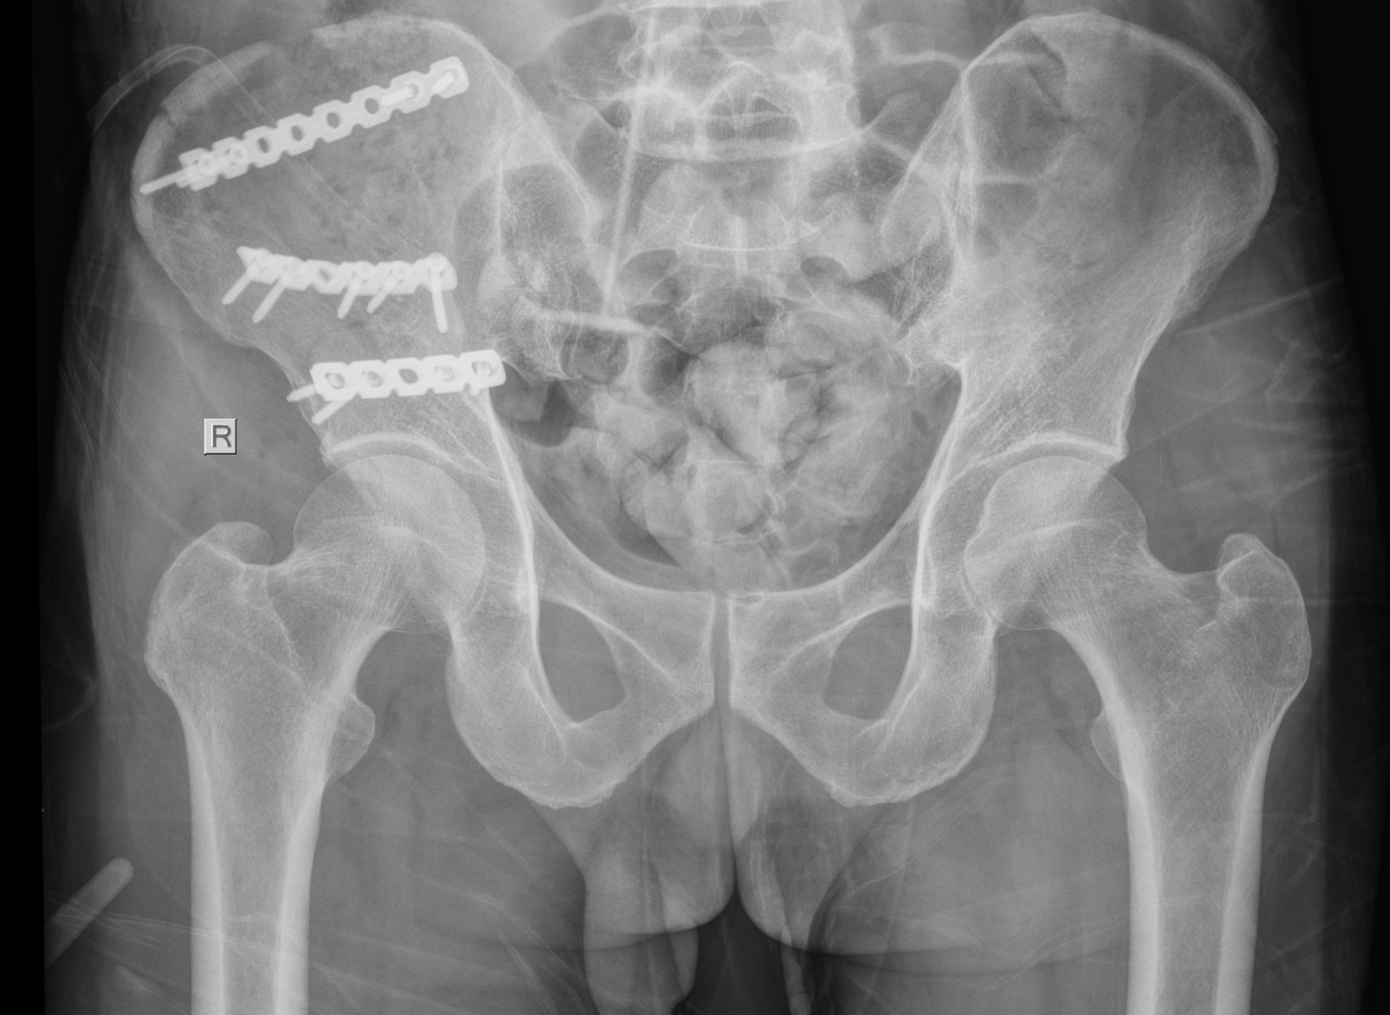

| Các bác sĩ thực hiện cuộc phẫu thuật kết hợp xương cho người bệnh |

Sau gần một tuần điều trị tích cực, thể trạng ông N. dần ổn định. Ê-kíp phẫu thuật đã lên kế hoạch can thiệp, tiến hành ca mổ kết hợp xương ổ cối – cánh chậu bằng nẹp vít. Ca phẫu thuật kéo dài hơn 2 giờ diễn ra thuận lợi, dưới sự phối hợp đồng bộ của các bác sĩ, điều dưỡng gây mê hồi sức và phẫu thuật viên.